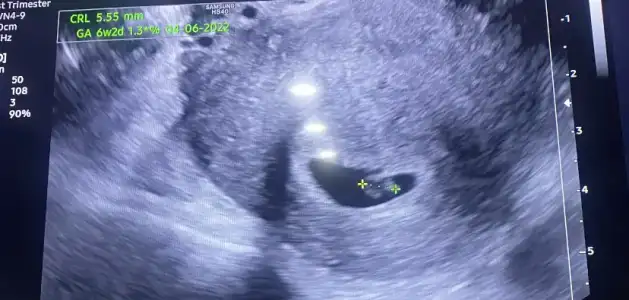

tabi inşallah 2500 olmuştur :) kafadan hesapladım en son değerimi baz alarak. bende vajinadan görmek istemiyorum korkuyorum biraz. karından görmeye yeter umarım. akşama güzel haberleri vereceğim kısmetse![]()